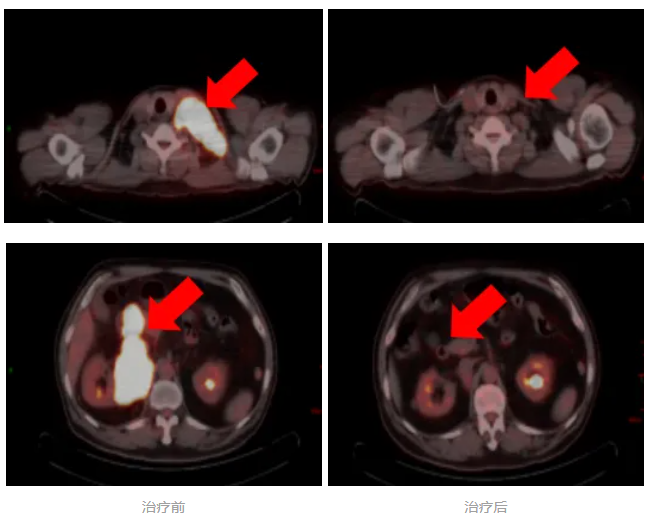

日前,一例高危、双表达型弥漫大B细胞淋巴瘤患者,在我院淋巴瘤及头颈肿瘤内科接受个体化精准治疗后,病情得到有效控制,疗效评价达到完全缓解(CR)。

经4周期治疗后,评估为部分缓解(PR)。为改善患者预后,MDT团队再次讨论并与患者沟通后,在后续治疗中加用组蛋白去乙酰化酶抑制剂。完成系统治疗后复查显示,患者最终达到完全缓解。